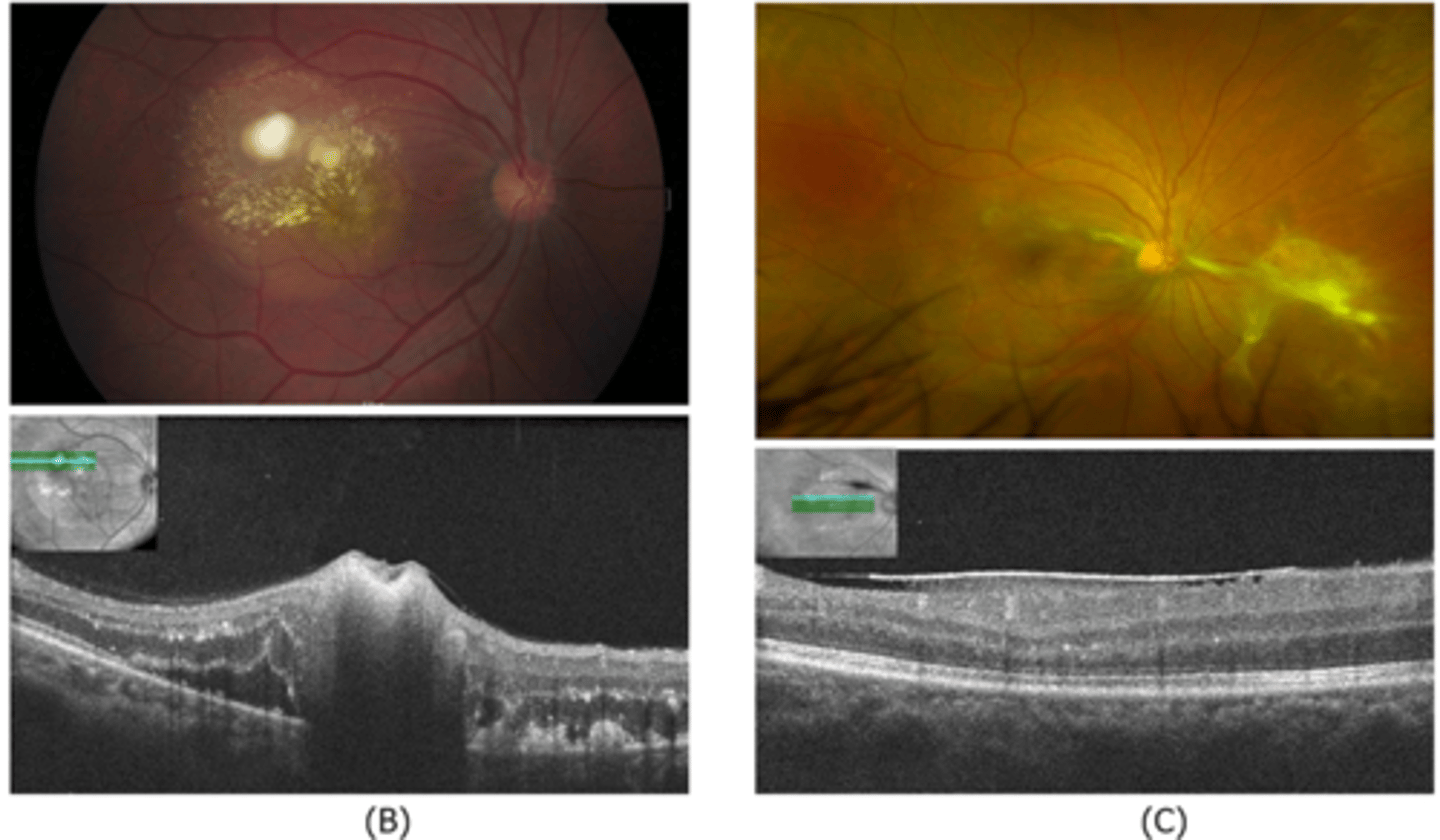

How does choroidal rupture appear on OCT here?

loss of RPE continuity at site of rupture = inner choroid atrophy

How does choroidal rupture appear on OCT here?

RPE disruption

+/- hemorrhage

What findings of degenerative myopia are seen here?

PPA

crescent

lacquer cracks